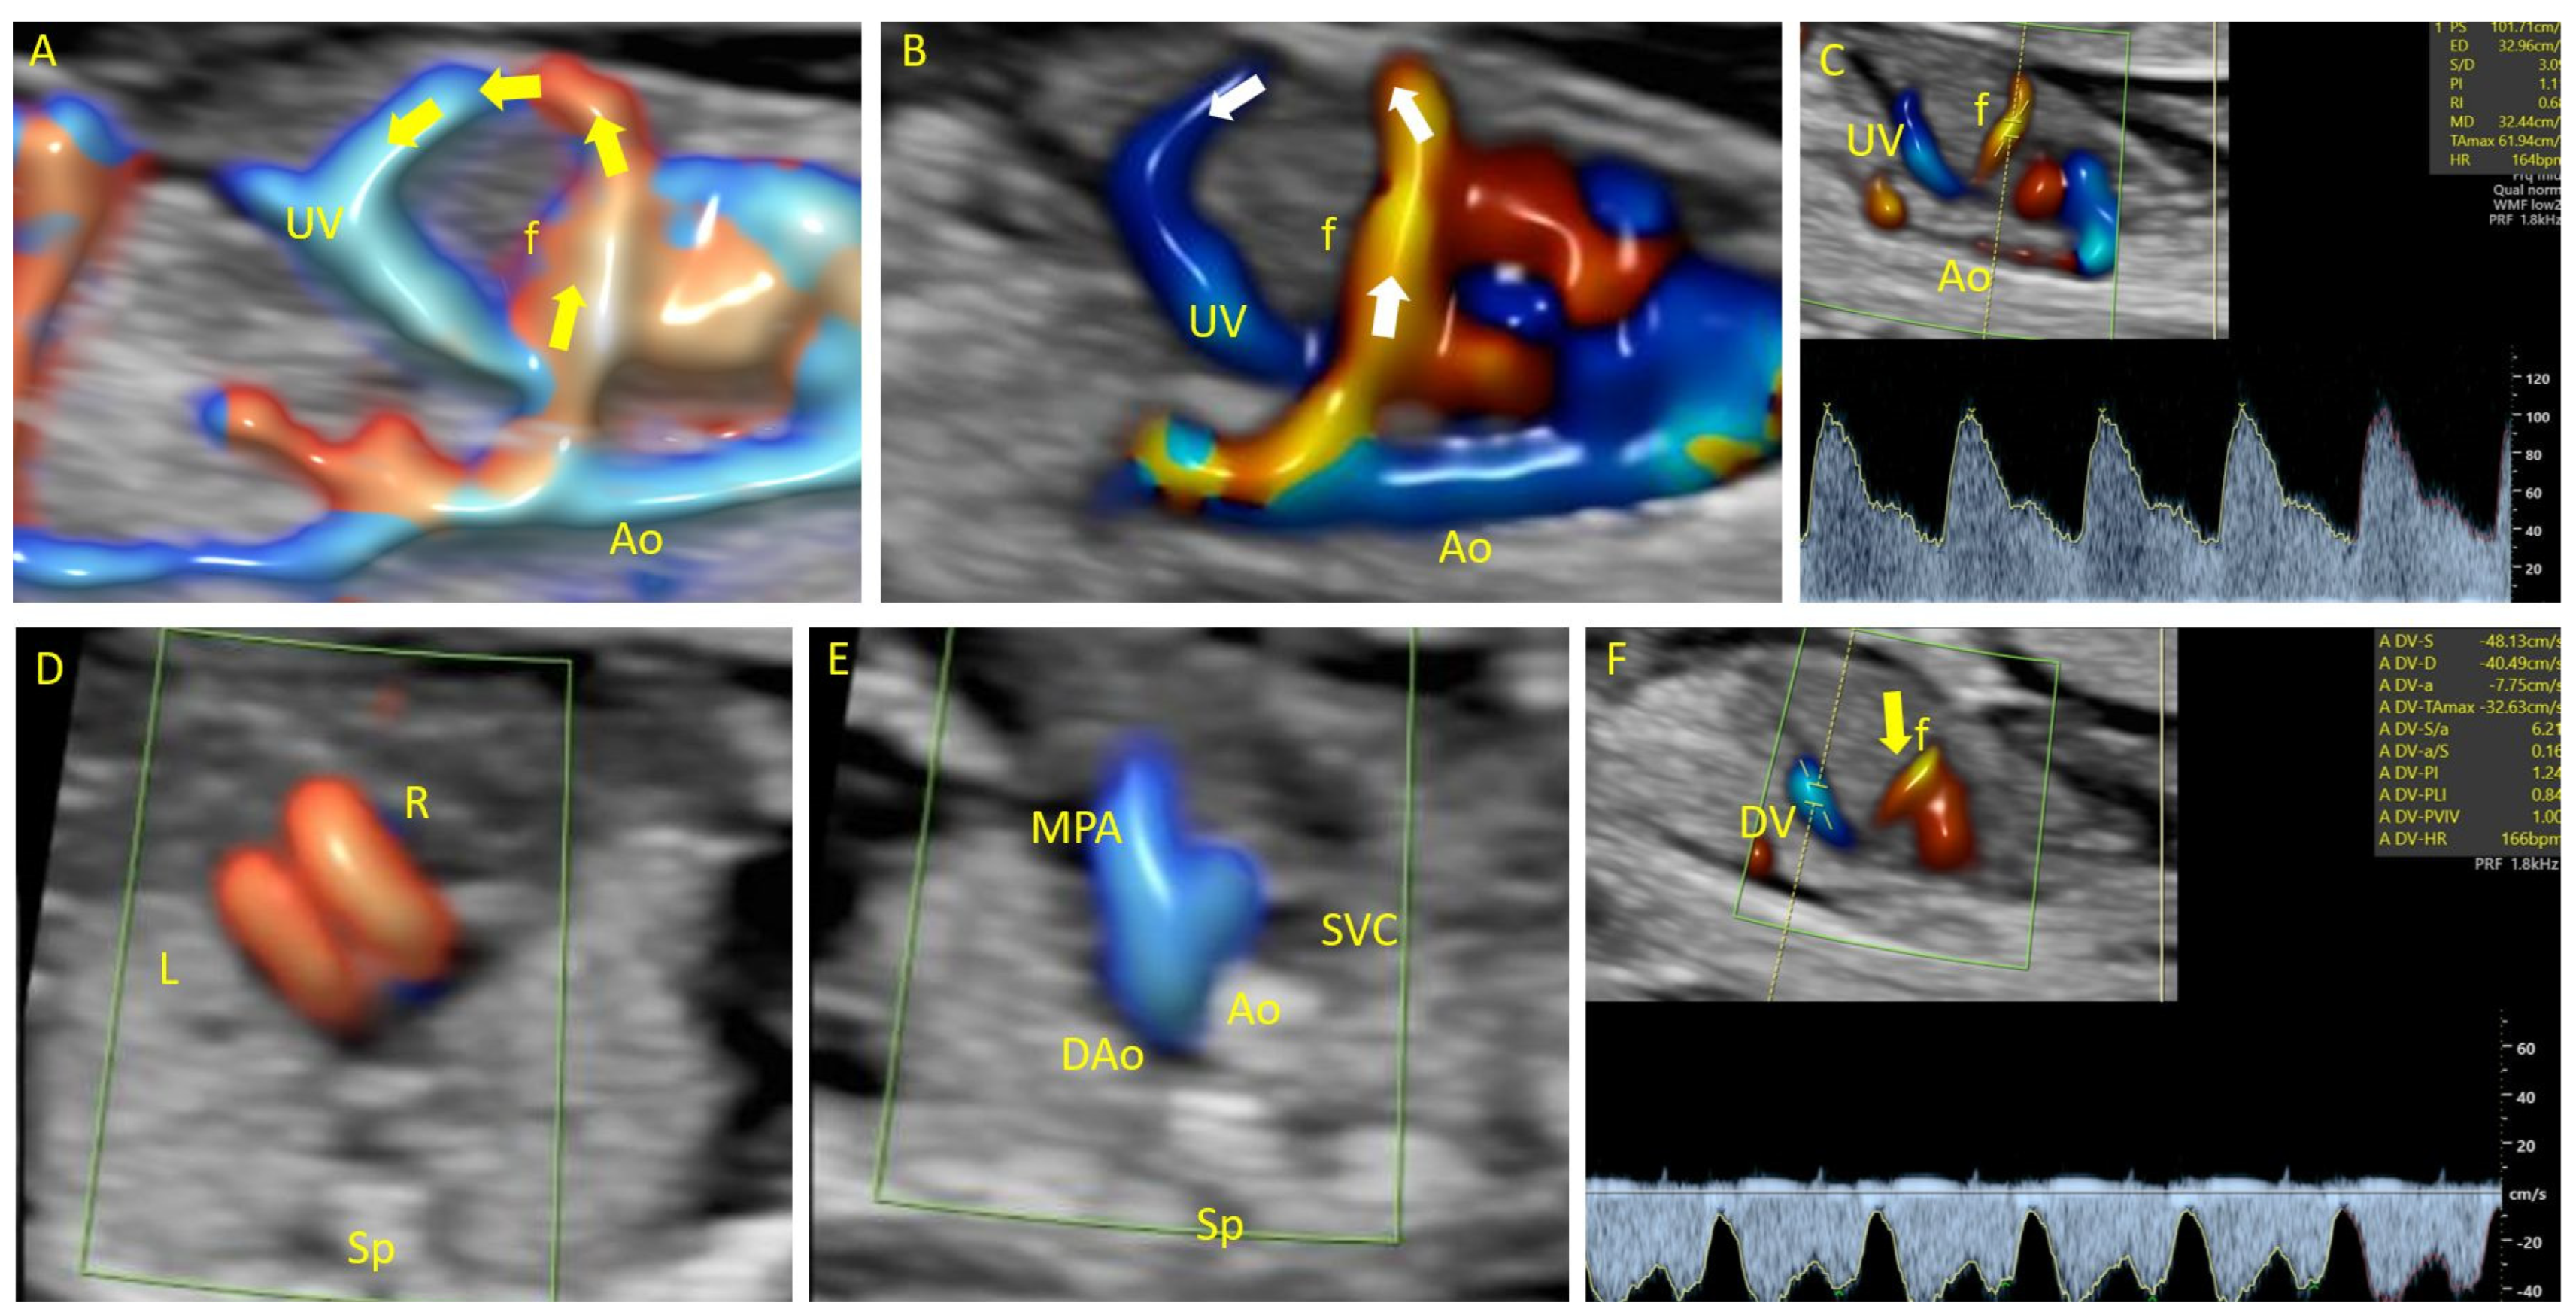

| 1 | 17 | Atypical vessel | Dilation of right heart chambers, early IUGR, hypotelorism, dysplastic kidneys, hydrops fetalis | Aorta-umbilical vein | Arterial flow | Follow-up | Fetal distress | 45X | Not applicable | Abortion at 19 WG |

| 2 | 19 | Intrahepatic arteriovenous complex malformation | Vermian malrotation, partial agenesis of the corpus callosum, frontal bossing, low nasal bridge, dilation of right heart chambers | Aorta-umbilical vein | Arterial flow | Follow-up | Fetal distress | Mosaic trisomy 17 | Not applicable | Abortion at 22 WG |

| 3 | 22 | Atypical vessel | Hydrocephalus, corpus callosum hypoplasia | Aorta-umbilical vein | Arterial flow | Follow-up | Stationary | Normal | Not applicable | Abortion at 23 WG |

| 4 | 13 | Atypical vessel | Cystic hygroma PVSA | Aorta-umbilical vein | Arterial flow | Follow-up | Fetal distress | Not performed | Not applicable | Abortion |

| 5 | 13 | Atypical vessel | Bilateral radius agenesis | Aorto-hepatic vein | Not evaluated | Follow-up | Stationary | T18 | Not applicable | Abortion |

| 6 | 13 | Atypical vessel | Megacystis, hand and foot malposition, skeletal malformations, hygroma, hemivertebra, VSD absent CSP | Aorta-umbilical vein | Not evaluated | Follow-up | Fetal distress | Not performed | Not applicable | Abortion |

| 7 | 13 Twin pregnancy | Atypical vessel | Absent | Aorta-umbilical vein | Arterial flow | Follow-up | Fetal distress | T21 | Not applicable | IUD of the affected fetus |

| 8 | 30 | Dilated vascular channels within the liver | Dilation of right heart chambers | Aorto-hepatic vein | Arterial flow | Follow-up | Stationary | Normal | Embolization of the fistulous tract | Death due to cardiac failure |